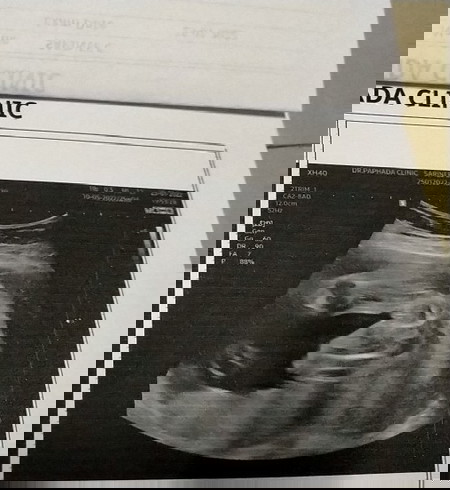

#ท้องแรกคะ อยากทราบว่าน้องจะเป็นผู้หญิง 100%ใหมค่ะ ดูไปดูมาเหมือนน้องจะออกจู๋ด้วยอ่ะคะ ขอดูภาพอันตร้าซาวด์ของแม่ๆหน่อยคะ

ของคุณแม่เหมือนมีจู๋เลยคะดูไม่เป็นกลีบส้มของผู้หญิงเท่าไหร่เลย

คุณหมอบอกว่าหญิงร้อยเปอร์เซ็นต์ค่ะ เพราะน้องมีกลีบเห็นชัดด

ถ้าเป็นผช.จะเป็นแบบนี้ค่ะ